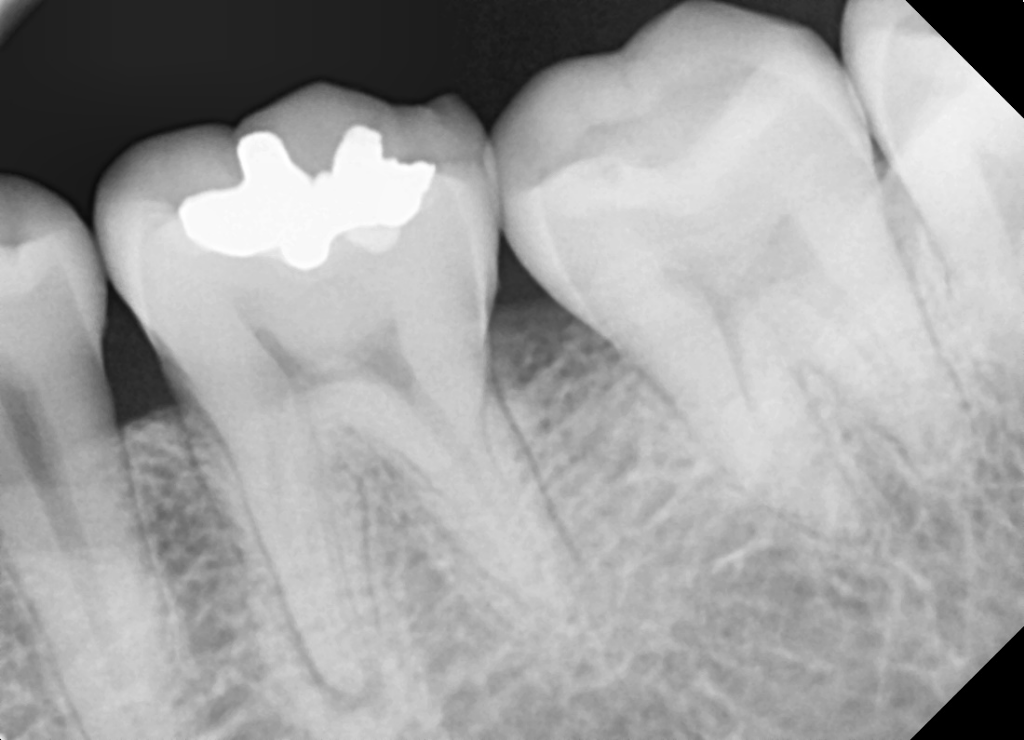

다른쪽 미세한충치도 병원 전부 다 그냥 써도 될거같다고 하는데 이곳만 인레이를 이야기하네요. 엑스레이 사진 올려봅니다. 엑스레이는 크라운씌우기 전 엑스레이입니다.

엑스레이 사진상으로는 신경치료를 하고 크라운 치료를 한 치아가 보이진 않습니다. 하지만 신경치료까지 하고도 증상이 사라지지 않앗다면 올려 놓은 치아상태라면 발치 즉시 식립을 하셔도 될것같습니다.

임플란트를 하는 경우에 발치를 하고 나면 치아에 뿌리가 있던 부분이 빈 공간이 남기 때문에 골이식을 하는 경우도 있습니다.